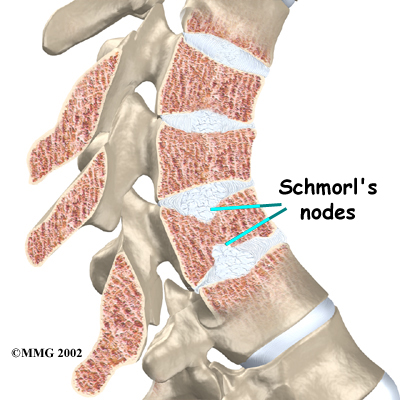

Each vertebral body is separated by an intervertebral disc, which acts like a cushion between them. There is a vertebral end plate between each disc and vertebral body. Sometimes in patients with Scheuermann's disease the material inside one or more of the discs squeezes through the vertebral end plate (which is often weaker in patients with Scheuermann's disease). This disc material forms pockets of material inside the vertebral body, a condition called Schmorl's nodes.

Taken from the side, an X-ray may show vertebral wedging, Schmorl's nodes, and changes in the vertebral end plates. Doctors use X-ray images to measure the angle of kyphosis. An official diagnose of Scheuermann's disease is made when three vertebrae in a row wedge five degrees or more and when the kyphosis angle is greater than 45 degrees.